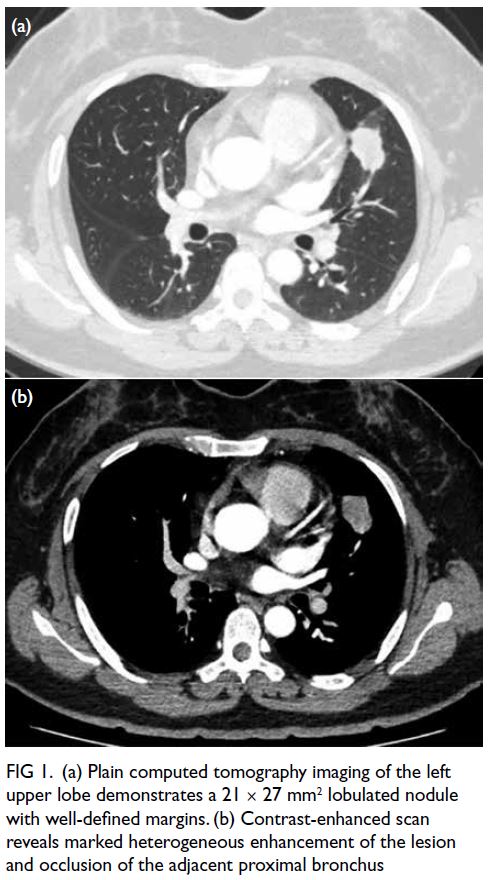

Contrast-enhanced chest computed tomography

demonstrated a lobulated left upper lobe nodule

with heterogeneous enhancement and partial

bronchial obstruction (Fig 1). Magnetic resonance

Figure 1. (a) Plain computed tomography imaging of the left upper lobe demonstrates a 21 × 27 mm2 lobulated nodule with well-defined margins. (b) Contrast-enhanced scan reveals marked heterogeneous enhancement of the lesion and occlusion of the adjacent proximal bronchus